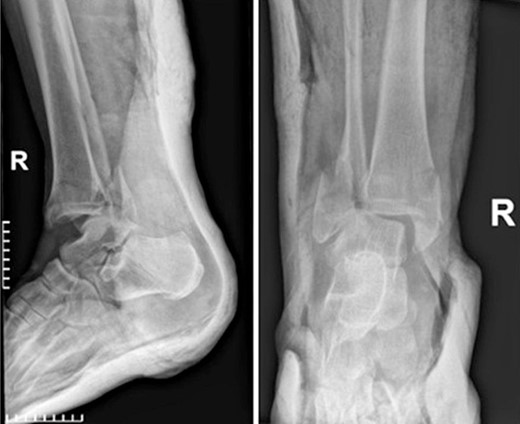

A 55-year-old female patient was admitted to the emergency department of our hospital due to an inability of weight bearing following a fall from standing height. Her medical history was unremarkable, with no significant records or regular medication use. Radiological evaluation revealed a trimalleolar fracture of the right ankle. Consequently, a cast was applied for pain management, and no weight-bearing was allowed on the affected limb (Fig. 1).

Anteroposterior and lateral X-ray of the ankle joint showing the trimalleolar fracture.